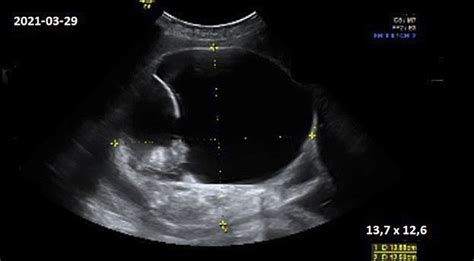

Gydytojas vaisiaus padėtį gimdoje vertina nuo 36 nėštumo savaitės, apčiuopdamas ir švelniai paspausdamas nėščiosios pilvą, bei klausydamas vaisiaus širdies tonų. Dažniausios ir normalios vaisiaus padėtys yra:

Vaisiaus pozicija nurodo, ar jis gimdoje pasisukęs priekiu, nugara ar šonu. Dažniausiai pasitaiko galvinė pirmeiga (kai vaikelio galva yra apačioje), tačiau pasitaiko ir sėdmeninė ar kojų pirmeiga, kurios gali reikalauti specialaus gimdymo būdo.

Jei vaisius įsitaisęs netaisyklingai, svarbu žinoti, kad iki 28 nėštumo savaitės tai nėra kritinė situacija, nes vaisius dar gali apsiversti pats. Tačiau iki 34-36 savaitės, jei vaisius nesusiskuba apsiversti, vietos trūkumas gali sutrukdyti jam tai padaryti vėliau.